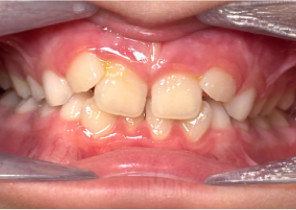

Case Report 2

7 years 11 months old, 24 stages of Invisalign® Palatal Expanders

Courtesy of Dr. David R. Boschken

Post Invisalign Palatal Expander Expansion

Post Invisalign Palatal Expander Treatment